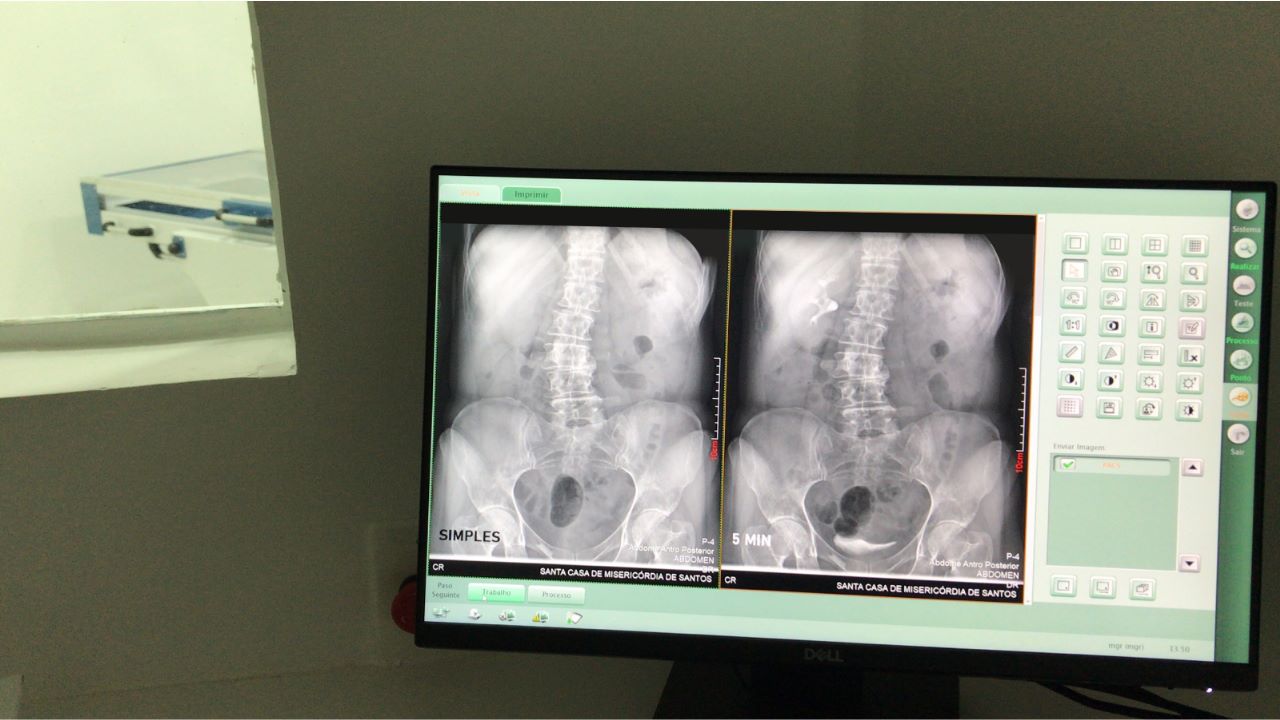

Recentemente, o hospital ampliou o serviço e entregou mais uma sala de exame no 2ºF, equipada com aparelho de alta tecnologia para aquisição de imagens, igual aos equipamentos existentes no PS Particular e Traumatologia SUS, com receptor DR e software capazes de captar e revelar imagens em até 2 segundos. Outro diferencial do equipamento é a mesa basculante que permite a realização segura de todos os exames da radiologia convencional com alta qualidade.

Raio - X digital: O raio-x digital é um tipo de radiografia que utiliza equipamentos digitais para capturar raios x e gerar imagens automaticamente para o computador. Esta modalidade elimina o processo de revelação do filme, economizando tempo, agilidade na emissão de laudos, maior qualidade da imagem, processo ecologicamente correto e armazenamento digital. Os raios x são capturados através de uma placa de circuitos sensíveis à radiação e a imagem é enviada diretamente para o computador. Este tipo de radiografia não utiliza intervenção humana e transfere a imagem na mesma hora. Além disso, o paciente tem menor exposição à radiação, pois as imagens são obtidas com níveis mais baixos de exposição à radiação comparados ao método analógico, aumentando a segurança do procedimento.